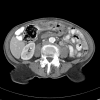

Intussusception of the large bowel is a rare clinical entity. In adults, this pathology is usually associated with a malignant lead point and often requires operative management. Reported is the case of an 83-year-old female who was recently diagnosed with superficial bladder cancer (T1) treated by partial cystectomy. She presented 3 months post-operatively with an isolated mucosal metastasis of the transverse colon causing intussusception and large bowel obstruction. The patient was successfully treated by colonic resection with primary anastomosis. Histology was significant for a pedunculated sarcomatoid bladder carcinoma originating from the colonic mucosa with incomplete invasion of the bowel wall. An isolated mucosal metastasis of this variety has not been reported in the literature to date.